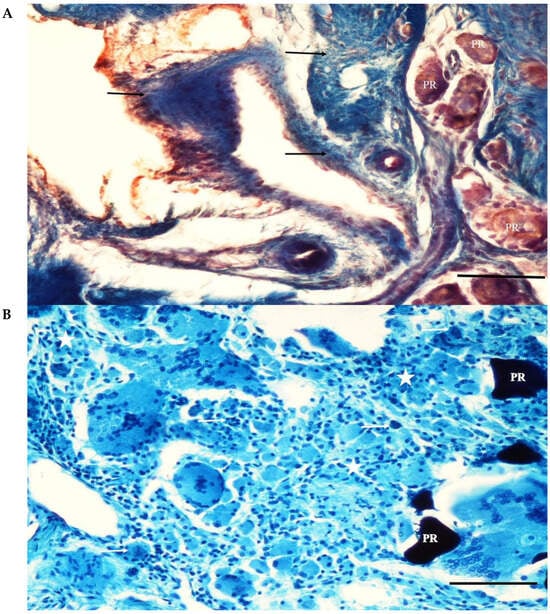

The screw bodies in the cortical region of the MP+ group were covered with tissue similar to that of the PC group. The eggshell particles were highly resorbed in the adjacent socket. Thin bone trabeculae lined with osteoblastic cells surrounded some of the particles. The interarticular region was filled with blood vessels and connective tissue rich in mononuclear cells. Intense mononuclear cell infiltration and a few multinucleated foreign-body giant cells were observed in some areas. Fibrous capsule formation surrounding the particles was not observed (Figure 8).

Figure 8.

(A) A section from the adjacent defect of the MP+ group. The eggshell particles (PR) are highly resorbed. Thin bone trabeculae (T) lined with osteoblastic cells (arrows) surround some of the particles. Pappenheim’s panoptic stain Magnification bar: 100 µm. (B) A section from the adjacent defect site of the MP+ group. Thin bone trabeculae (T) surround a highly resorbed eggshell particle (PR). Adipose cells (asterisks) and connective tissue rich in mononuclear cells (arrow) fill between the particle remnants. Intense mononuclear cell infiltration is evident. Fibrous capsule formation surrounding the particles is not seen. Haematoxylene-eosin staining. Magnification bar: 100 µm.

In the MP group, the particles were resorbed at different levels. Osteoblastic cells were seen as simple cuboidal cell lines on the surfaces of the graft particles. Primary bone trabeculae were found on some trabecular surfaces. Intense mononuclear cell infiltration and a few multinucleated foreign-body giant cells were observed in some areas. Fibrous capsule formation surrounding the particles was not observed (Figure 9).

Figure 9.

(A) Eggshell particles (PR) have resorbed at different levels, with some being large and others being small. The interparticular region is mainly filled with connective tissue and fibrocartilage (arrows). New bone formation is not seen. Trichrome staining. Magnification bar: 100 µm. (B) A section through the adjacent defect area of the MP group. The remnants of eggshell particles (PR) and the intervening areas are covered by dense connective tissue (asterisk) filled with mononuclear cells (arrow). Trichrome staining. Magnification bar: 100 µm.